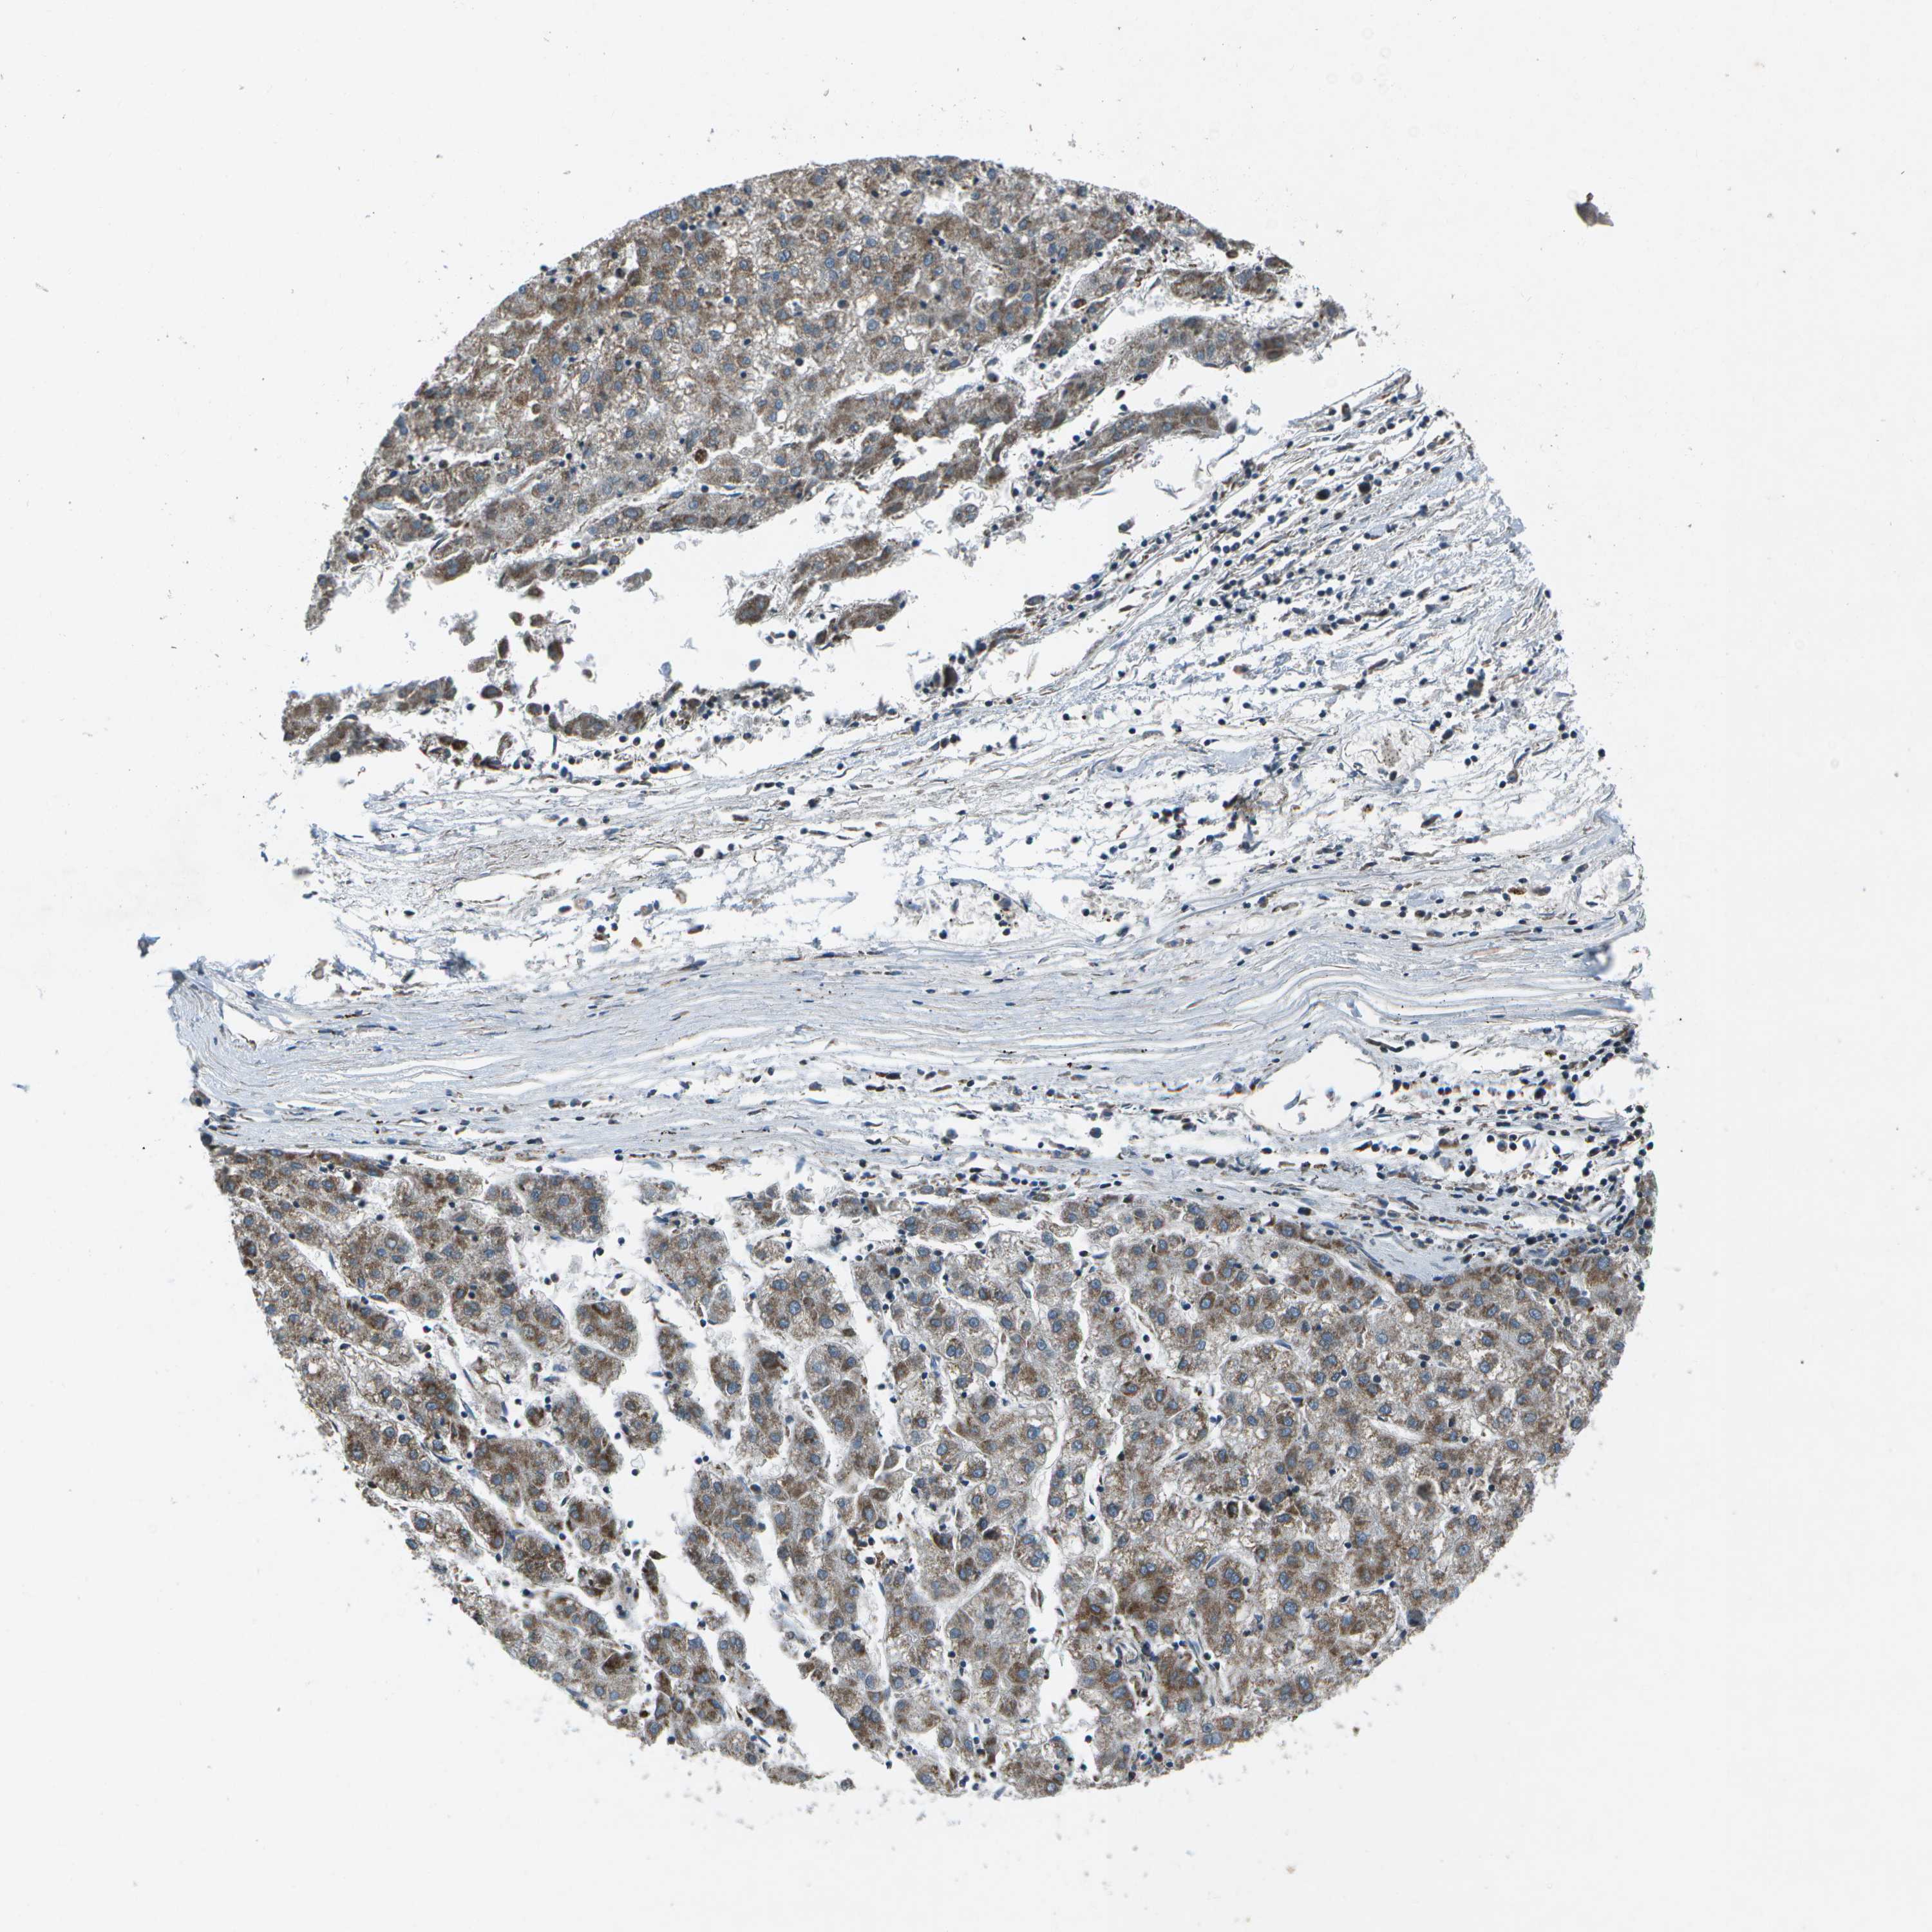

LIVER CANCER - Protein expressioni

A mouse-over function shows sample information and annotation data. Click on an image to view it in a full screen mode. Samples can be filtered based on level of antibody staining by selecting one or several of the following categories: high, medium, low and not detected. The assay and annotation is described here.

Note that samples used for immunohistochemistry by the Human Protein Atlas do not correspond to samples in the TCGA dataset.

Antibody stainingi

Antibody staining in the annotated cell types in the current human tissue is reported as not detected, low, medium, or high, based on conventional immunohistochemistry profiling in selected tissues. This score is based on the combination of the staining intensity and fraction of stained cells.

Each image is clickable and will lead to virtual microscopy that enables deeper exploration of all samples and also displays staining intensity scores, fraction scores and subcellular localization as well as patient and tissue information for each sample.

Antibody HPA016496

Antibody CAB022082

Staining

High

Medium

Low

Not detected

Intensity

Strong

Moderate

Weak

Negative

Quantity

>75%

75%-25%

<25%

None

Location

Nuclear

Cytoplasmic/membranous

Cytoplasmic/membranous,nuclear

Cholangiocarcinoma

Carcinoma, Hepatocellular, NOS